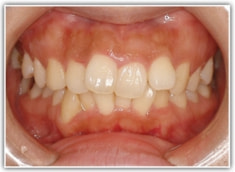

上顎前突ケース

治療法:表の矯正(T21ブラケット)

治療前

治療後(2年後)